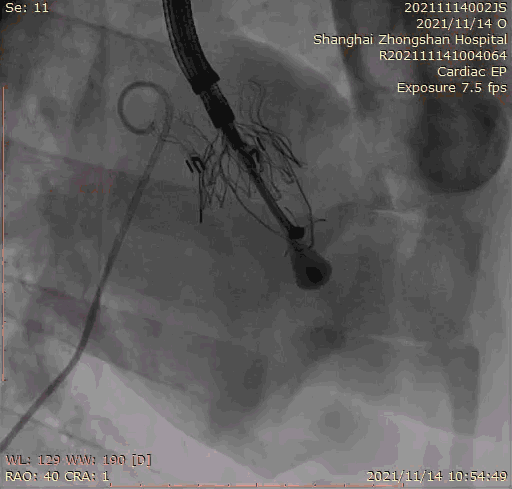

上海中山醫院葛均波院士、錢菊英院長、周達新教授、潘文志教授、潘翠珍教授、李偉教授共同完成此次臨床前研究。術后葛均波院士對Lux-Valve Plus的器械操作性能給予了高度評價,DSA和超聲影像也顯示出在本次研究中Lux-Valve Plus的安全性和有效性俱佳。

本次臨床前研究經右側頸靜脈置入LuX-Valve Plus輸送系統可調彎鞘管,在DSA及超聲引導下將人工三尖瓣瓣膜植入到原有三尖瓣位置,利用獨特的錨定技術將人工瓣膜支架可靠固定在預定的位置。